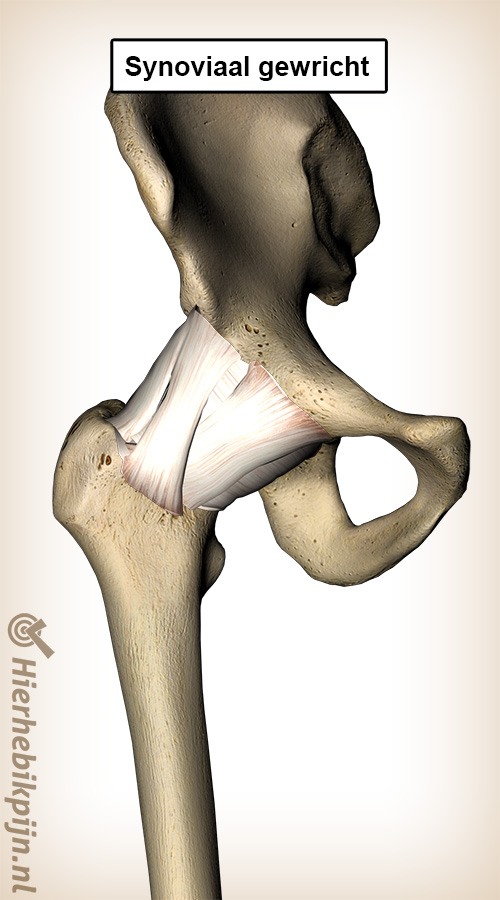

page_id_30_lead

page_id_30_body